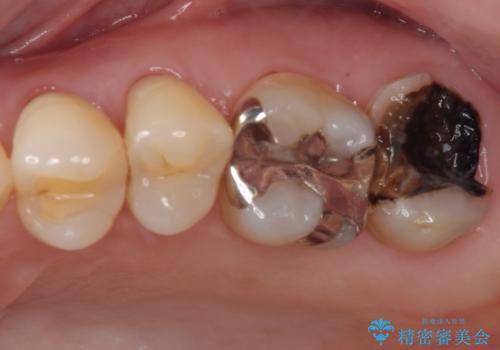

奥歯がしみる オールセラミッククラウンによる奥歯のむし歯治療